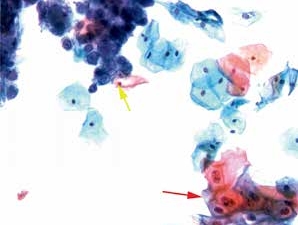

图4-50 角化型鳞癌(高倍、液基、巴氏染色)

肿瘤素质:变性细胞、坏死性碎片及陈旧性出血。此为鳞癌与HSIL的鉴别点之一,浸润性宫颈鳞癌常伴有肿瘤素质。

图4-51 角化型鳞癌(中倍、液基、巴氏染色)

肿瘤素质:坏死性碎片、纤维蛋白及陈旧性出血。HSIL的背景相对干净,鳞癌常伴有肿瘤素质。